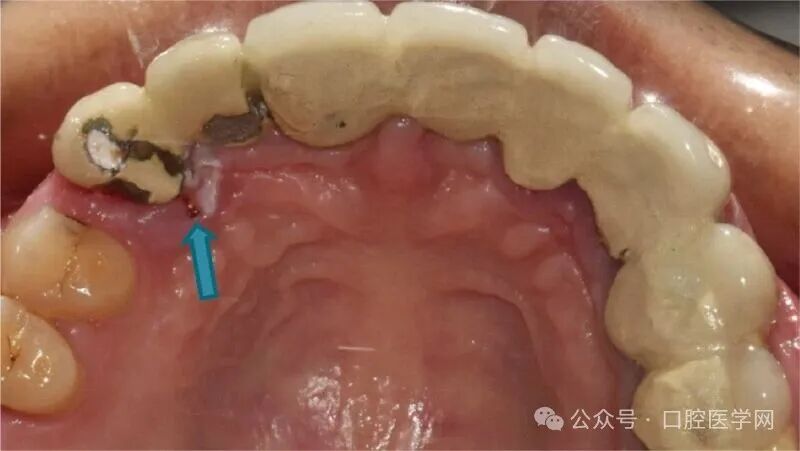

口外及口内体格检查除感觉异常外,其余均未见异常。口外检查显示从上唇到眶下区域15-20毫米范围内存在明显的感觉改变,如图1所示。口内检查发现右上尖牙的烤瓷冠上有临时充填物,腭侧可见牙龈退缩伴组织脱落,透过该区域能够看到牙胶尖,如图2所示。患者主诉右上象限牙龈特别是尖牙和前磨牙区域有刺痛感。该牙齿叩诊时有轻度不适,颊侧牙龈沟未见肿胀。

图2 口内术前照片显示13号牙腭侧牙龈退缩伴脱落。